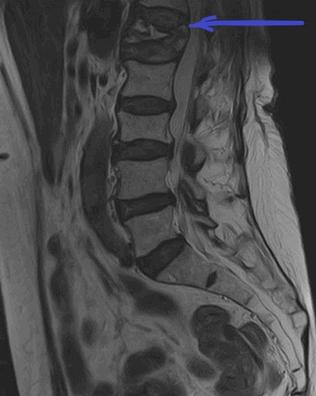

МРТ пояснично-крестцового отдела позвоночника. На Т2-ВИ в сагиттальной плоскости определяется компрессионный перелом L1 позвонка на фоне остеопороза.

МРТ покажет изменение формы позвонка, линию перелома, дефекты костной замыкательной пластины. Может меняться высота между позвонками. Если к перелому привела слабость костной ткани, на снимках кость выглядит более светлой из-за снижения содержания солей кальция между костными трабекулами.

Компрессионный перелом виден на рентгене при достаточной степени деформации позвонка, хорошо визуализируется на КТ во всех случаях. МРТ выгодно отличается тем, что показывает свежий перелом. Это определяет тактику лечения – максимально щадящий режим для спины, иммобилизация корсетом. Также он выявляет сопутствующую патологию дисков, грыжу, дегенеративные и воспалительные болезни позвоночника, суставов, спинного мозга и его оболочек, нервов, сосудов.